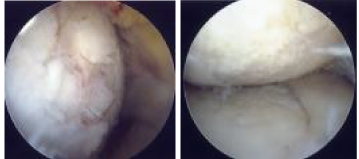

手術療法例-1 《関節鏡視下手術》

関節の周囲(皮膚面)に2~3箇所の小さな穴を開けます。その後関節に光ファイバーと小さな高性能カメラで構成された内視鏡を挿入して損傷部位を修復したり、不要な遊離体や損傷組織を摘出除去します。変性した半月板や軟骨、増生した滑膜や骨棘の処理も行います。

傷口も小さく、手術後数日で歩行可能で、早期に社会復帰ができます。ただし、効果の持続性が短い場合もあり、症状が進行している場合には適応とならないことが多い手術方法です。